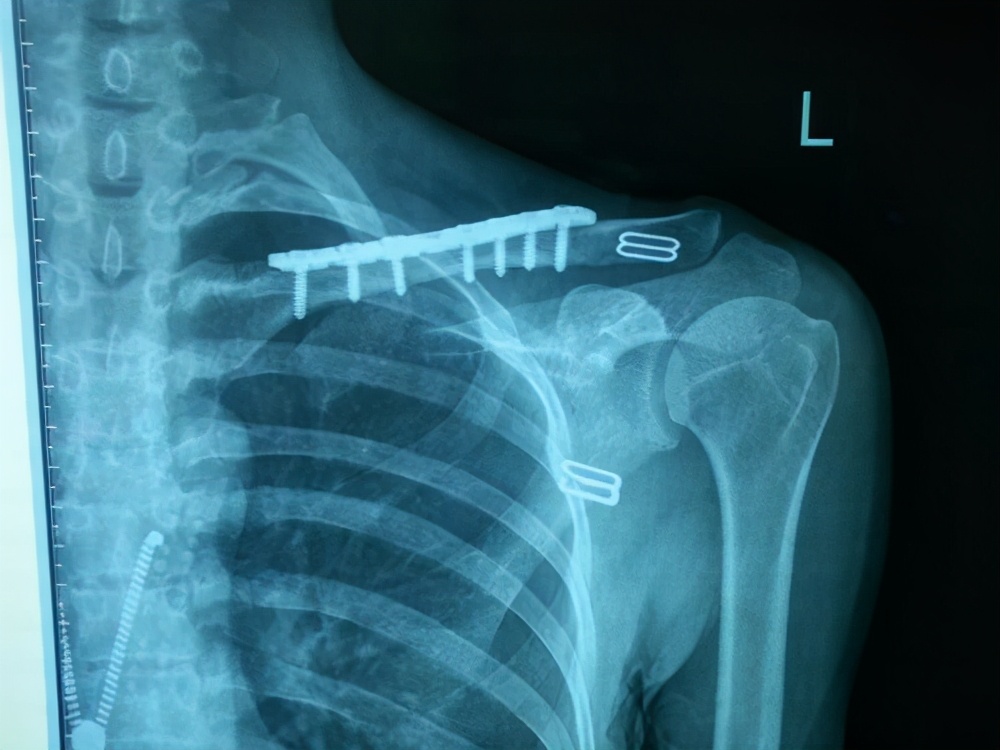

锁骨直板

4、影响外观:比如锁骨常规板子,因为位置浅表,就在皮下,最后钢板突出了,非常影响患者夏天的穿衣,如果骨折愈合了建议来取。